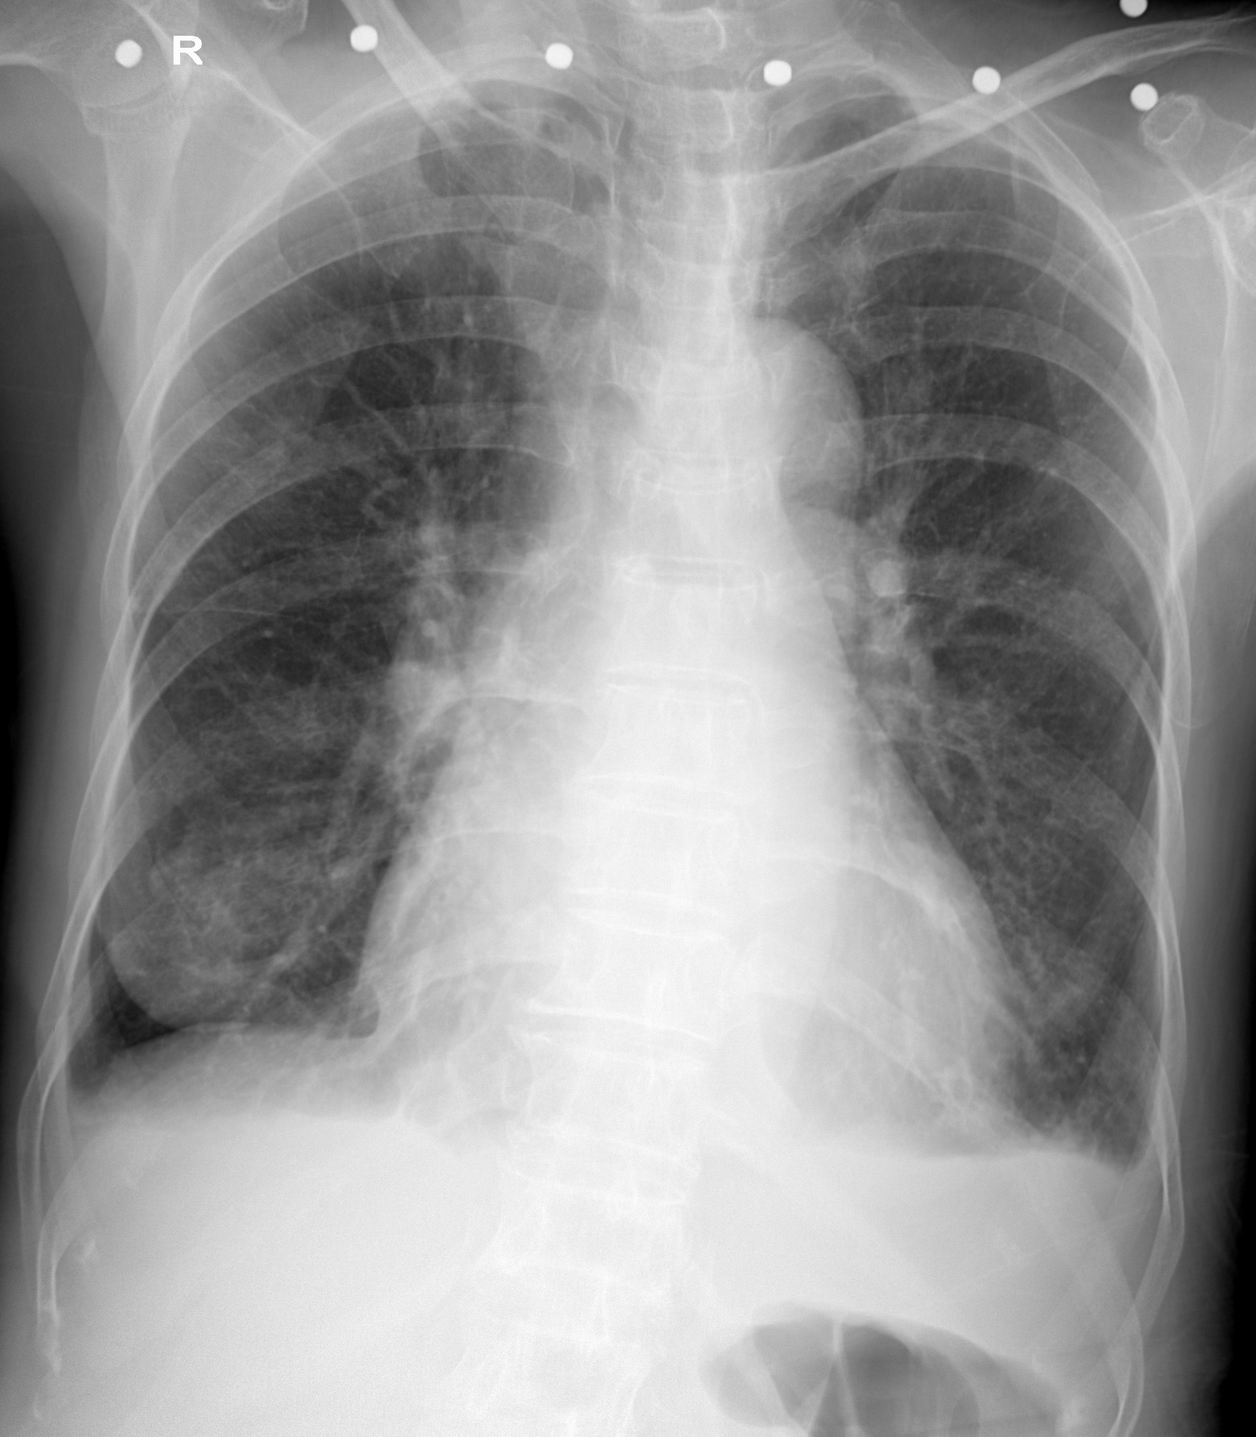

女,74岁,直肠癌术后肝转移,以间断性咳嗽、气喘、呼吸困难6年加重伴纳差5天为主诉入院。bp:120/40mmhg,神清,双肺呼吸音粗,可闻及干湿性啰音。肝位于锁骨下288mm,质韧、边钝,压痛明显,肝区叩击痛阳性。

双肺转移可能性大,建议ct检查。另双侧少量胸腔积液,心包积液待排。

1双肺转移可能性大,双侧少量胸腔积液,建议ct检查2                                                                        2心包积液待排

双侧少量胸腔积液,,心影增大。

左侧心缘旁似见类圆形密度增高影考虑肺转移可能性大,双侧少量胸腔积液,建议ct检查

胸部平片未见肺野内明确转移性病变。

两肺中下肺野慢性支气管炎并胸膜炎改变。

双侧少量胸腔积液,心影增大。

建议:必要时行ct扫描检查。